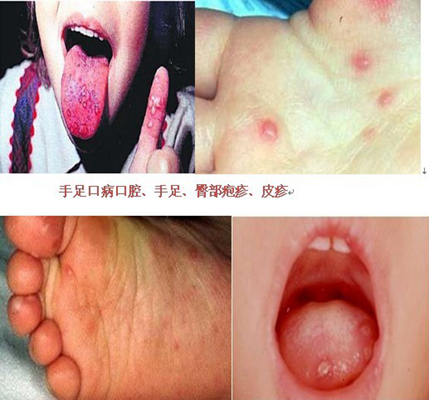

手足口病圖片

A:判斷小孩手足口病往往要根據特徵性的表現,手足口病顧名思義是小嬰兒這個年齡段出現口腔或者咽部,以及手心、足底有皰疹,這種皰疹的表面有時候會有鮮紅色的,有時候還會有點潰破,這就要高度懷疑是手足口病。臨床上要確診的話,一般有時候還要做腸道病毒的檢……

A:對於小兒手足口病來講,是由於病毒感染所引起來的,臨床症狀上主要表現為以下兩個方面,就是孩子會出現發熱、精神略有些弱,以及出現食慾的下降。皮膚會出現皮疹,尤其是在手、足、臀部會出現斑疹或者皰疹,還有在口腔黏膜以及咽部都會出現皰疹,所以孩子咽……